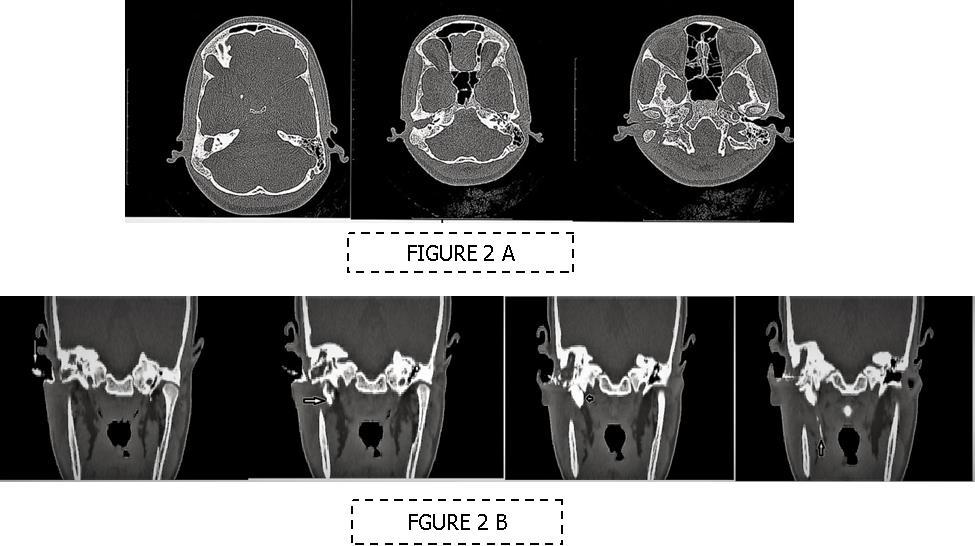

A 13 year old girl presented in ENT outpatient department with complains of recurrent right ear purulent discharge from pre and post auricular area for last 5 years. She had a history of incision and drainage in right post auricular area six months prior for similar complain. On local examination, there was right Grade II8microtia with atretic External Auditory Canal (EAC) and pre-auricular skin tag (Figure 1). A small fistulous opening was also seen in right cavum conchae region. Left ear examination was normal with intact tympanic membrane. Tuning fork tests using 256 and 512 Hz tuning forks showed moderate to severe conductive hearing loss in right ear with Rinne’s test positive in left ear. HRCT scan of temporal bones showed membranous atresia of right EAC with grade II microtia. Soft tissue density was seen filling the EAC and the entire middle ear cavity (Figure 2A). A CT based fistulogram done four months before our consultation identified multiple fistulous tracts situated in post auricular region and anterior to stylomastoid foramen in inframastoid region. These fistulous tracts were communicating through middle ear cavity (Figure 2B). There was associated erosion of posteroinferior and anteroinferior wall of EAC. Ossicles were dysplastic or eroded. Inner ear structures were normal. Patient underwent right radical mastoidectomy with wide conchal meatoplasty under general anaesthesia. Intraoperatively, there was right EAC membranous atresia with fistulous opening in cavum conchae. Cholesteatoma sac was seen filling the mastoid antrum area extending into middle ear cavity and EAC with erosion of posterior canal wall. Except remnant of malleus head which was fixed to epitympanic wall, no other ossicle was found. Oval window area showed bony depression without any overlying stapes footplate (Figure 3). Lateral semicircular canal bulge, facial nerve canal and chorda tympani were found at their usual locations (Figure 4). Obliteration of mastoid cavity posterior to vertical segment of bony facial canal was done using pedicled temporalis muscle flap to reduce the size of postoperative cavity. Middle ear cavity was covered with temporalis fascia graft.

Figure 2.(A-B) HRCT imaging. (A) Right canal atresia with soft tissue density behind it (B) CT sino-gram showing multiple (arrow marked) sinuses communicating to right middle ear cavity.

(A-B) HRCT imaging. (A) Right canal atresia with soft tissue density behind it (B) CT sino-gram showing multiple (arrow marked) sinuses communicating to right middle ear cavity.